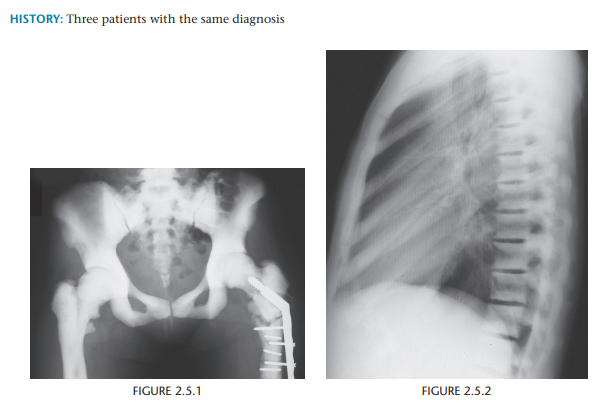

Osteopetrosis

Osteosclerosis + alternating radiolucent bands +metaphyseal widening = osteopetrosis.